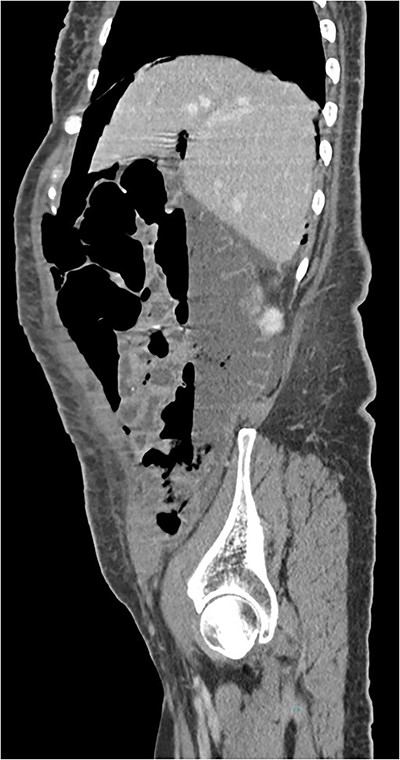

A 55-year-old woman was being followed in a gynecology consultation for a large abdominal mass, likely of adnexal origin (370 mm in its largest dimension). She underwent a hysterectomy, bilateral adnexectomy, and segmental enterectomy due to an iatrogenic perforation of a small bowel loop. On the seventh postoperative day, due to the absence of intestinal transit since surgery, an abdominal X-ray was requested, and general surgery was consulted, suspecting pneumoperitoneum. In this context, the patient underwent a CT scan, which revealed “pneumoperitoneum in the free cavity, significant for one week postoperative, with about 4 cm anteroposterior diameter in the epigastric region. There is also a significant amount of retroperitoneal air in the left pelvic cavity, extending to the presacral space. There are no gas bubbles immediately adjacent to the surgical suture lines.” (Figs 3 and 4). Blood tests showed no significant alterations, and clinically, the patient was hemodynamically stable with only mild tenderness on abdominal palpation, without guarding. Based on the clinical, laboratory, and imaging findings, it was decided to keep the patient on a nil-by-mouth diet with clinical observation. The next day, the patient resumed intestinal transit, allowing for the reintroduction of an oral diet. Blood tests showed no increase in inflammatory markers. The patient continued to progress favorably during the remainder of her hospital stay and was discharged on the tenth postoperative day.